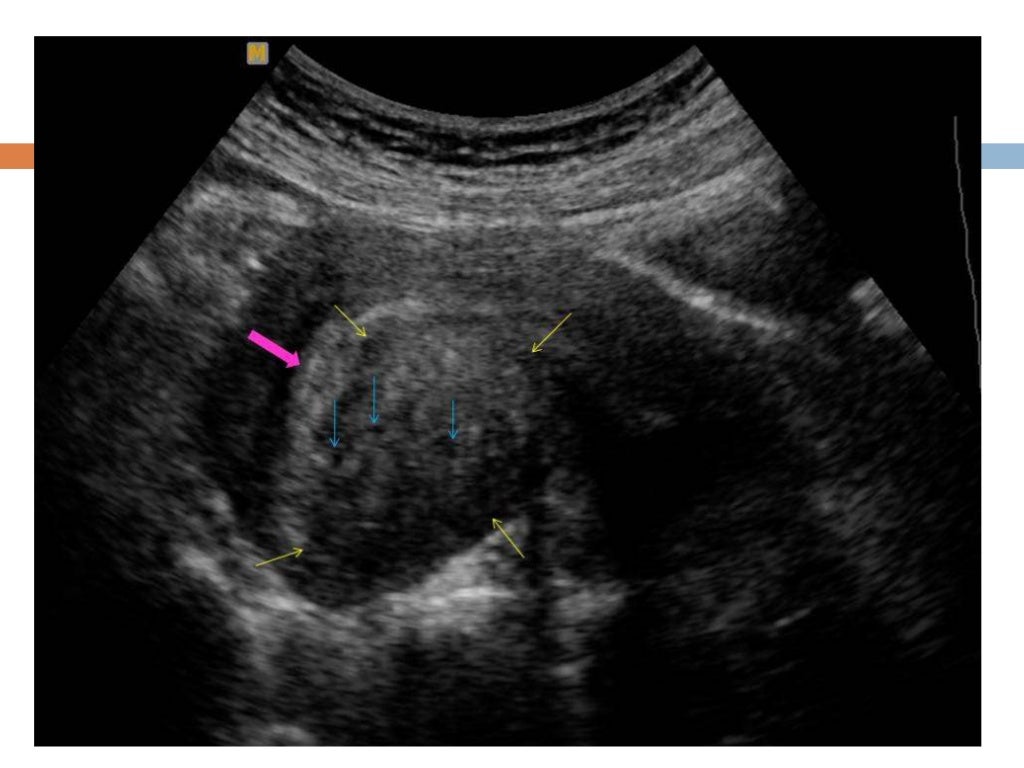

Фиброма матки узи картина - фото презентация